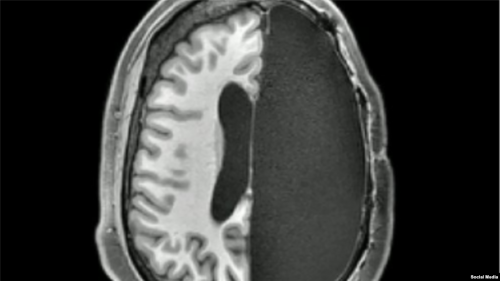

دراسات جديدة: اكتشاف مذهل.. ماذا يحدث بعد إزالة نصف الدماغ؟

أظهرت مسوحات جديدة أن أدمغة البشر التي تم استئصال نصفها خلال مرحلة الطفولة، تستطيع مواصلة نشاطها.

أظهرت مسوحات جديدة أن أدمغة البشر التي تم استئصال نصفها خلال مرحلة الطفولة، تستطيع مواصلة نشاطها بشكل مذهل.

ومن المعروف أن عمليات استئصال الدماغ طورت في عشرينيات القرن الماضي، لعلاج أورام المخ الخبيثة، لكن نجاحها في الأطفال الذين يعانون من تشوهات في الدماغ أو نوبات عصبية أو أمراض يقتصر ضررها على نصف الدماغ مثل الصرع، أذهل حتى العلماء المتمرسين.